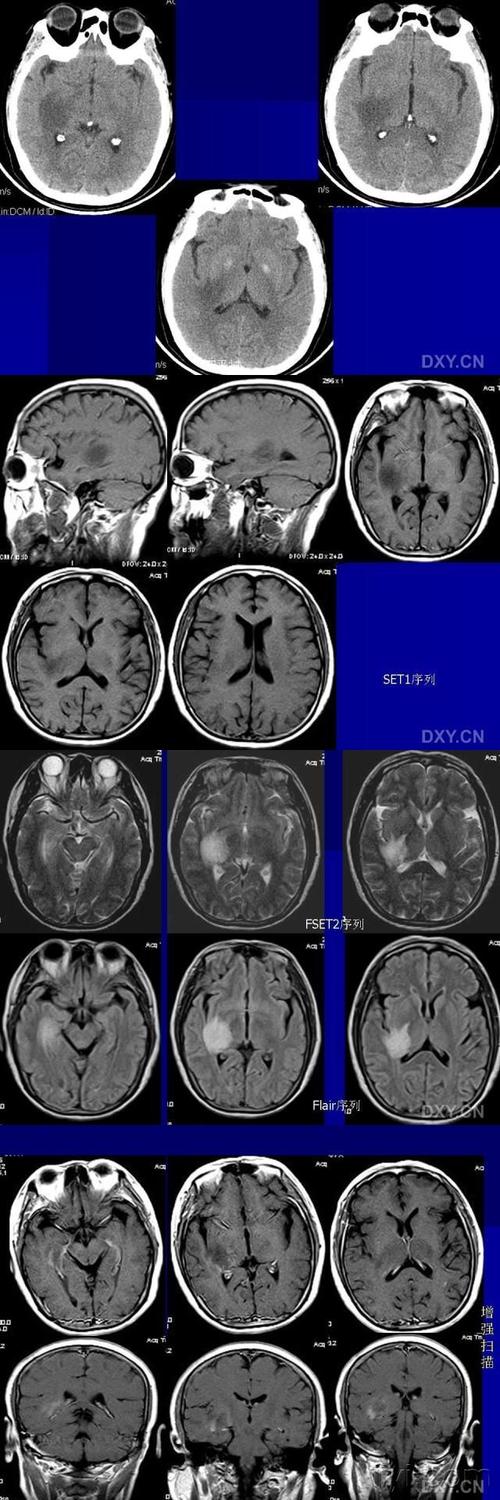

脱髓鞘假瘤临床常以急性起病为主, 为脑实质孤立性或多发性占位性病变

磁共振显示脱髓鞘病变,考虑先天发育不良,需要治疗吗?

脑白质脱髓鞘CT

脑白质脱髓鞘病变

脱髓鞘核磁共振图

炎性脱髓鞘

脑白质脱髓鞘图片